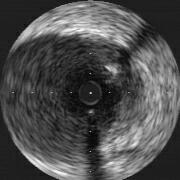

LAD#6をculpritととする不安定狭心症患者さんに、1週間ヘパリン、NTGの点滴

後、PCI致しました(画像;pre)。PercuSurgeによるdistal protectionをD1の手前

に施行し(画像;POBA)、POBA施行。吸引して造影してみると、ちょうどprotection

balloonの手前のところに血栓象らしきものを認めました(画像;POST1)。時間経過と

共にどんどんと血栓が大きくなり、くっきりとしたものとなったのですが(画像;

POST2)、この血栓像らしきものができた原因はなんでしょうか。protection

balloonの留置部にも実は不安定なプラークがあって(preのIVUSではLADはmidのあた

りまで全周性に少しプラークがありましたが、それほど不安定プラークに特徴的とさ

れる所見はみあたりませんでした。)、そこをballoonで障害した結果、血栓が付着

していったのか。あるいは、病変部をballoonningしたことで破砕されたプラークの

内容物が飛んで、protection balloonの手前のところに付着し、それが原因で血栓が

形成されていったのでしょうか。よろしくご教授下さい。

pre

POBA

post-1

post-2